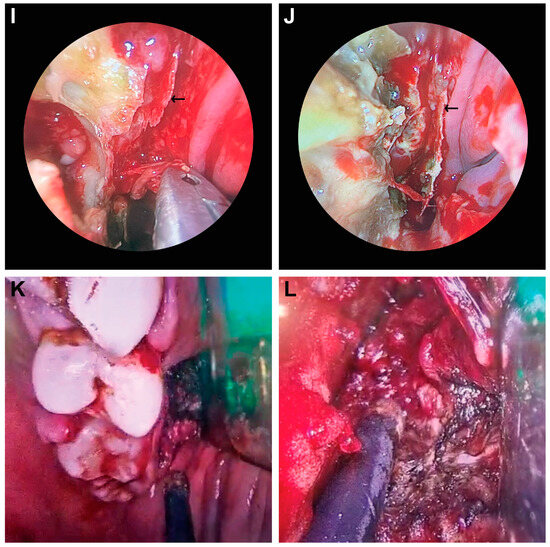

The immobility of the eye, exophthalmos, incomplete or complete blepharoptosis, and swelling of the zygomatic region were observed in the facies (Figure 1). Figure 2 shows CT and MRI preoperative radio-imaging aspects, and Figure 3 shows intraoperative aspects during FESS.

Figure 3.

Intraoperative aspects during FESS in CAM. (A–D) Extensive mucosal necrosis in the right nasal cavity; periorbital fat is highlighted by *. (E) Denudation and fungal infiltration of the hard palate; (F) oronasal fistula at the junction between the apparently healthy tissue and the infected tissue mass; (G) fungal invasion in the right nasal cavity with secondary perforation of the nasal septum (arrow); (H) polypoid degenerate rhino-sinusitis; (I,J) the fungus-infiltrated nasal septum detached in bloc during the operative cure; (K) bone erosion at the level of the left alveolar rim and gingival hemorrhage. Surgical exploration needed in order to practice hemostasis. (L) Cauterization in the zygomatic region.

Affection of the nasal fossa (Figure 3A–D,G–J) and the homolateral maxillary sinus was observed in all patients included in the study (Figure 2B,E,H). The extension of lesions to all paranasal sinuses on the same side was observed in half of the patients (50%, n = 4/8). The extension of the lesional process at the level of the orbit was observed in 62.5% of patients (n = 5/8) (Figure 1A–D and Figure 2A,D,F), 25% of patients (n = 2/8) presented oral invasion (Figure 3E,F,K), 25% of patients (n = 2/8) presented invasion in the zygomatic region (Figure 1B,D and Figure 2D,F), and one patient (12.5%, n = 1/8) presented cerebral invasion (Figure 2C).

All patients underwent FESS (Figure 3).